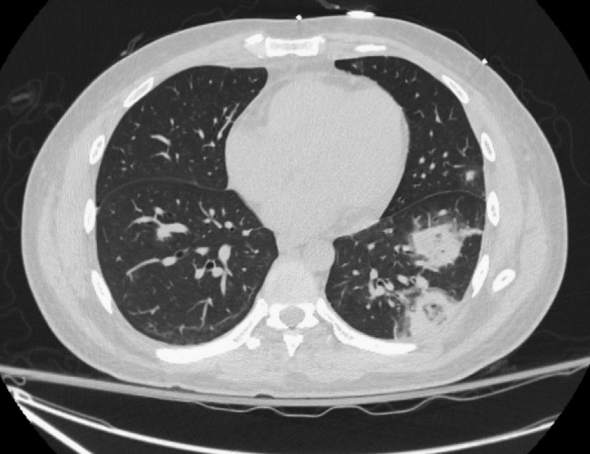

颈部增强CT扫描显示多发龋齿和左侧腭扁桃体肿大,并伴有周围炎性改变(图1)。胸部CT扫描显示双侧多发实性肺结节

图3 胸部CT显示左下叶有两个大的空洞性病变,沿血管分布处于不同的演变阶段